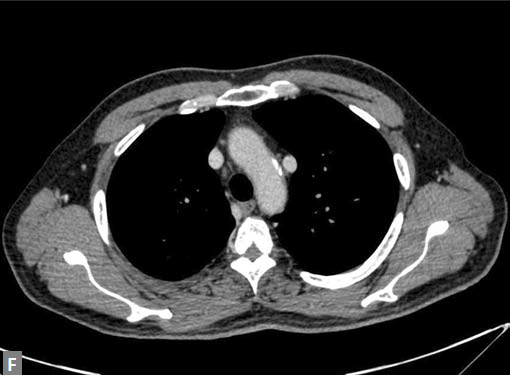

Figs 19A to Y (A to C) Scannogram (A), plain (B) and contrast study (C) show partial anomalous pulmonary venous connection; (D to F) Heterotaxy; (G) Aortic occlusion; (H and I) Aortic stents; (J) Aortic dissection with ‘Benz’ sign due to second dissection within the true lumen; (K, L and M) Aortic dissection with thrombus in pseudolumen following catheter angiogram; (N) Aortic dissection involving common carotid arteries and subclavian artery; (O, P, Q and R) Aortic dissection with right renal artery arising from true lumen and left renal artery from false lumen; (S, T, U and V) Stanford B dissection with extension Y to iliac vessels; (W to Y) Aneurysmal dilation of ascending aorta